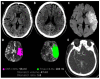

Endovascular therapy (EVT) has revolutionized the management of acute ischaemic strokes with large vessel occlusion, with emerging evidence suggesting its benefit also in large infarct core volume strokes. In the last two years, four randomised controlled trials have been published on this topic-RESCUE-Japan LIMIT, ANGEL-ASPECT, SELECT2 and TENSION, with overall results showing that EVT improves functional and neurological outcomes compared to medical management alone. This review aims to summarise the recent evidence presented by these four trials and highlight some of the limitations in our current understanding of this topic.